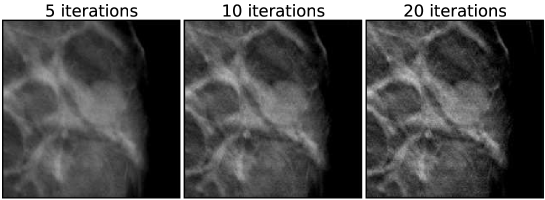

V.4 Case 1: microcalcifications

A set of EM images for the first case is shown in Fig. 4, and the corresponding ASD-POCS images are shown in Figs. 5, 6, and 7. A striking feature of the ASD-POCS reconstructions is the prominence of the microcalcifications. Lower values of accentuate these small features better than large -values. Even for , the visibility of the microcalcifications is comparable to that of the EM results. The differences in microcalcification contrast can be seen quantitatively in the profiles shown in Fig. 8. These profiles are plotted along depth and transverse lines that intersect with a single microcalcification. We point out that while lower increases regularization strength in ASD-POCS and lower iteration number increases regularization strength for EM, there is no direct correspondence between the two parameters; the chosen iteration numbers for the EM profiles are selected only for reference. Interestingly, there seems to be little change in the ASD-POCS image for iteration numbers 5-20, which obviously has some practical implication.

Each of the three cases, below, are reconstructed in the same way, meaning the same sets of algorithm parameters are used. The exceptions to this are that the image volume dimensions and the projection data cropping are slightly different for each case. For the EM results images are shown at 5,10, and 20 iterations, as iteration number is really the main control for regularization. For ASD-POCS, the objection function parameter is set to 0.8, 1.0, and 2.0; lower values of tend to sharpen edges. The relaxation factor takes on values of 1.0, 0.5, and 0.1; smaller , in general, allows for ASD-POCS to achieve lower values of the TpV objective. Images for ASD-POCS are also shown for 5, 10, and 20 iterations. As will be seen, there is surprisingly little change in the reconstructed images for these iteration numbers. In each of the image sets, a 2D ROI is displayed that shows either microcalcifications or a mass, depending on the case.